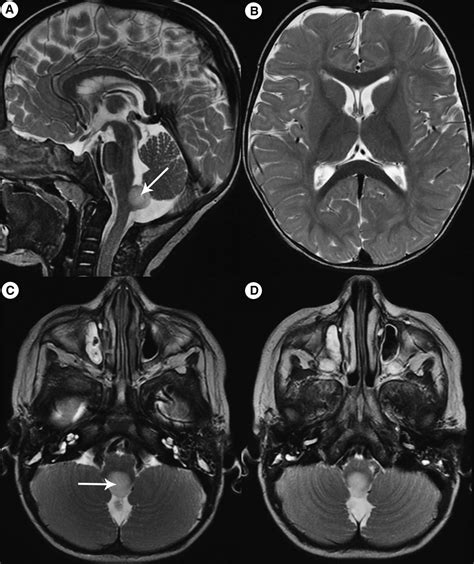

To appreciate how the Area Postrema Vomiting Center functions, it is essential to understand its anatomical location. It is situated in the medulla oblongata, specifically within the dorsal portion of the caudal brainstem. This area is classified as one of the circumventricular organs. Because these organs lack the tight junctions characteristic of the blood-brain barrier, they are considered "leaky" windows that allow the brain to monitor the systemic circulation directly.

The Area Postrema contains a dense network of fenestrated capillaries and specialized neurons. These neurons are highly sensitive to various neurotransmitters and circulating toxins. When substances such as chemotherapeutic agents, bacterial toxins, or certain drugs reach this region, the neurons fire, sending signals to the nearby Nucleus Tractus Solitarius (NTS). The NTS then coordinates the complex motor patterns required for vomiting, involving the diaphragm, abdominal muscles, and gastrointestinal tract.